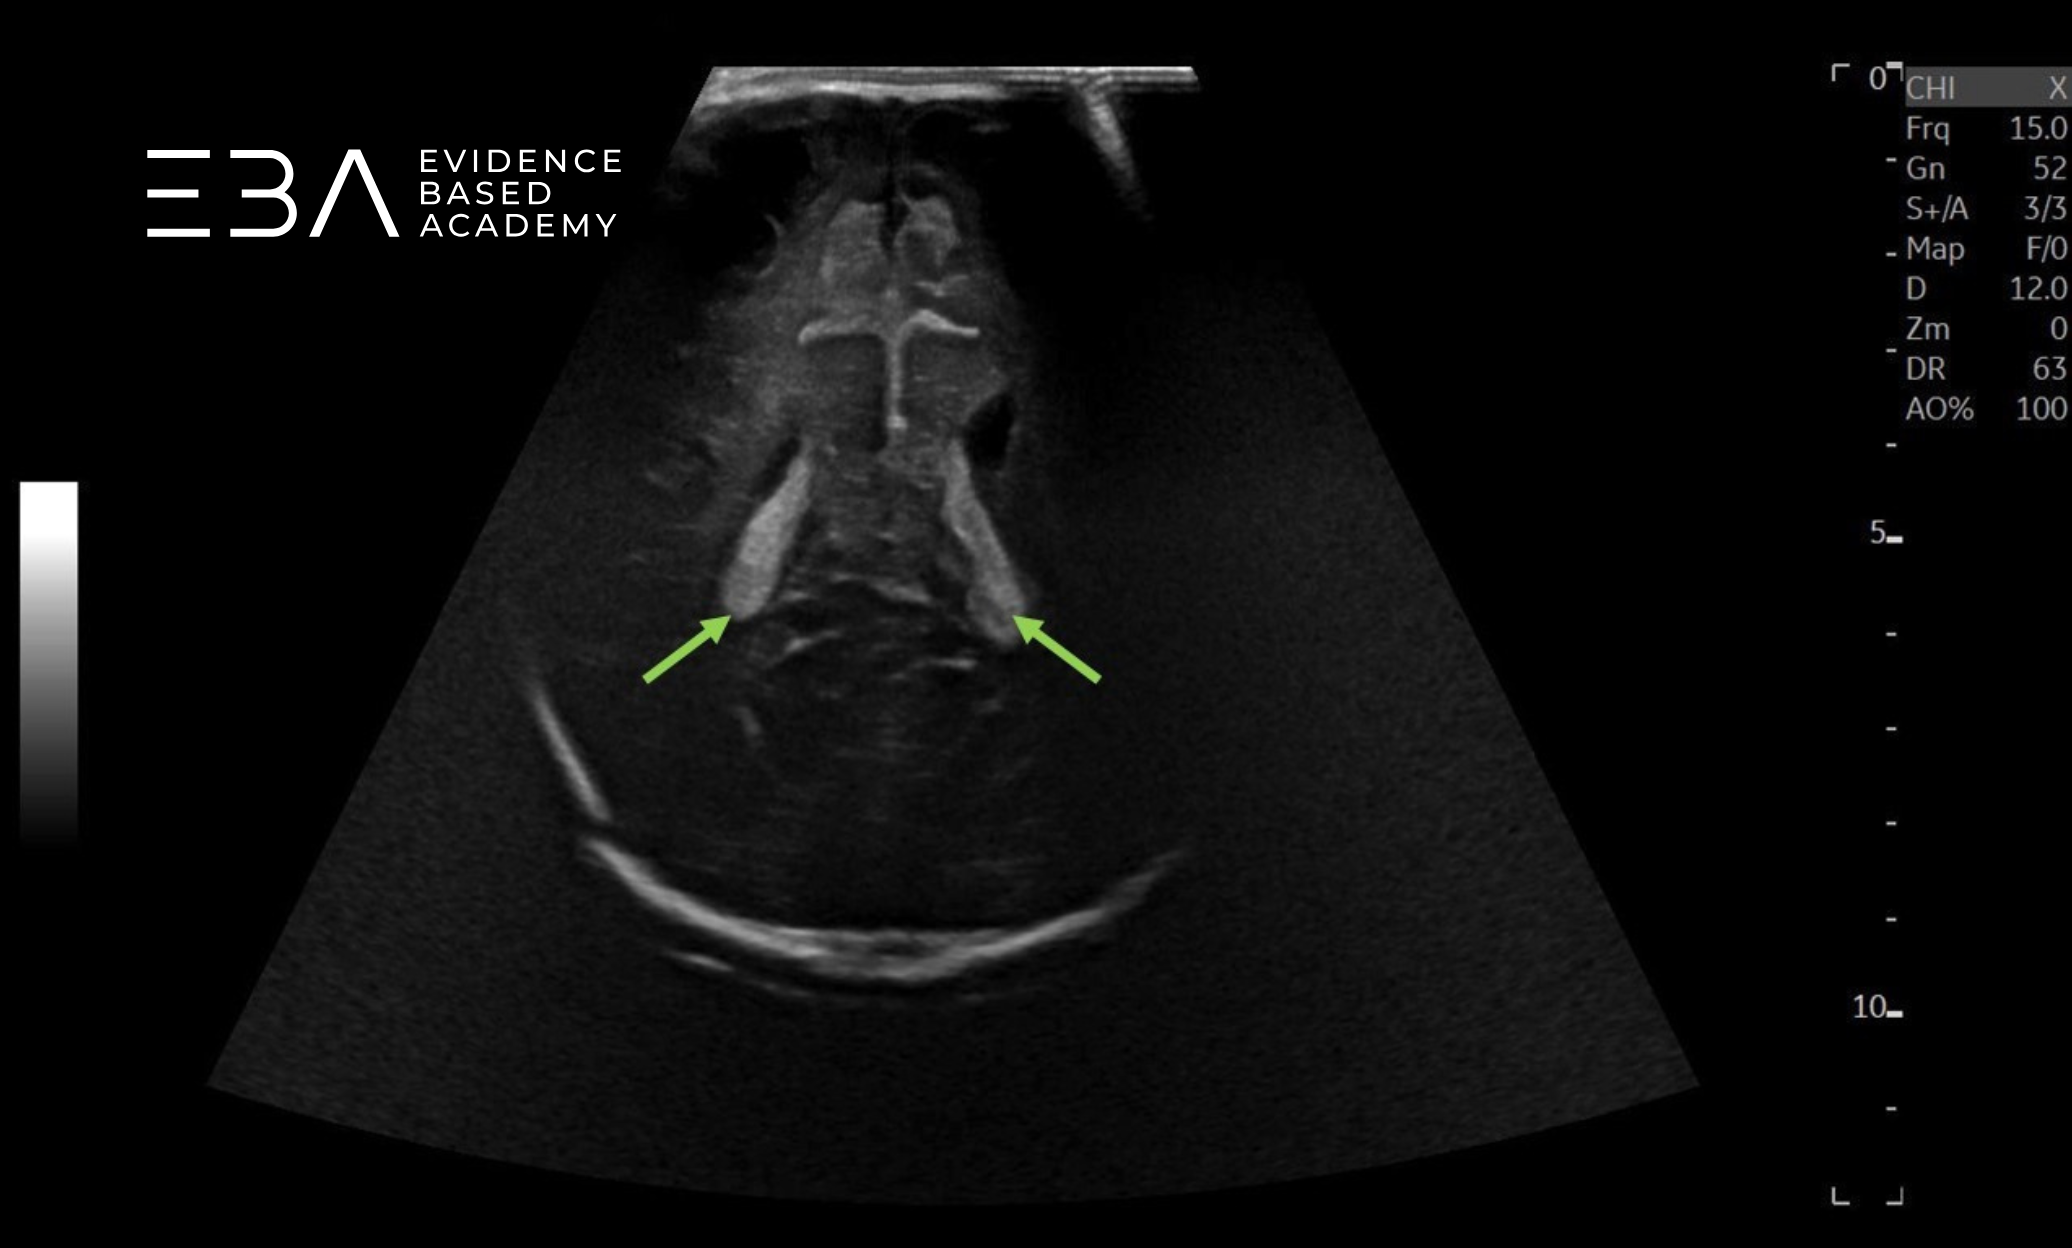

Głowica liniowa o wysokiej częstotliwości, czyli 10–18 MHz stanowi niezbędne uzupełnienie badania (1, 3, 5). Głowica ta generuje obraz o wysokiej rozdzielczości, umożliwiający szczegółową ocenę przestrzeni przymózgowej, opon mózgowych, przestrzeni podpajęczynówkowej i podtwardówkowej, kory mózgowej, bruzdowania mózgu i móżdżku (1, 3, 5). Ze względu na duży rozmiar i niższą penetrację ich zastosowanie może być ograniczonem szczególnie w ocenie odległych struktur, np. tylnego dołu czaszki przez ciemiączko przednie (3).

Obraz mózgowia w głowicy liniowej.